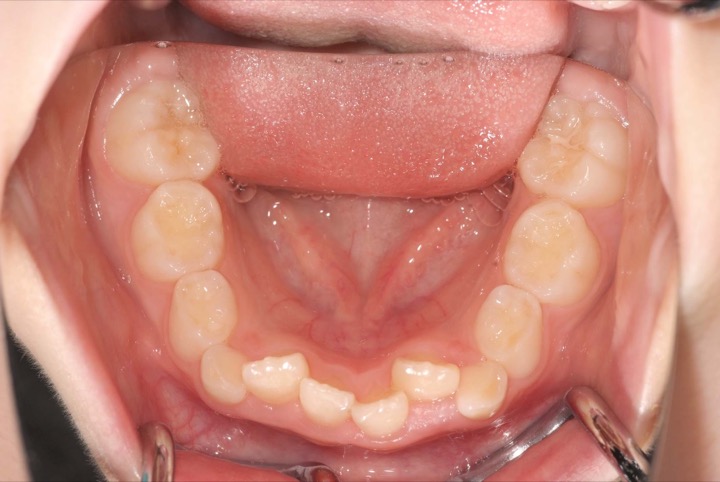

初診時年齢9才の女子で上下顎前歯の部の乱ぐいを気にして来院されました。

検査の結果、叢生と過蓋咬合を伴うアングルⅠ級不正咬合と診断しました。